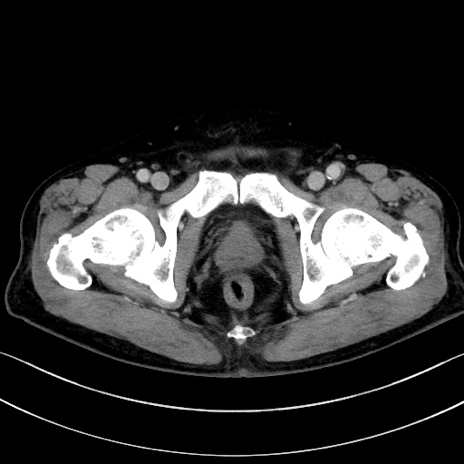

症例15(横断像)

【症例】70歳代男性

【主訴】腹痛

【現病歴】今朝から腹痛あり。全体的に痛い。特に左上の方。排ガスが今日はない。冷や汗が出る。

【既往歴】直腸癌術後

【身体所見】左側腹部〜上腹部に圧痛あり。腹膜刺激症状明らかなではない。軽度反跳痛。左下腹部に術後瘢痕あり。

【データ】WBC 7700、CRP 0.02